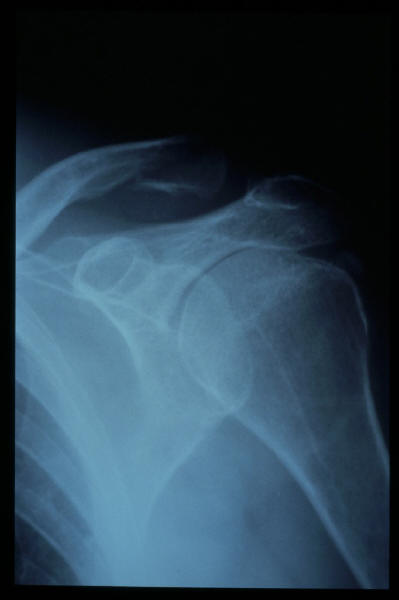

Fractura impactada de húmero .